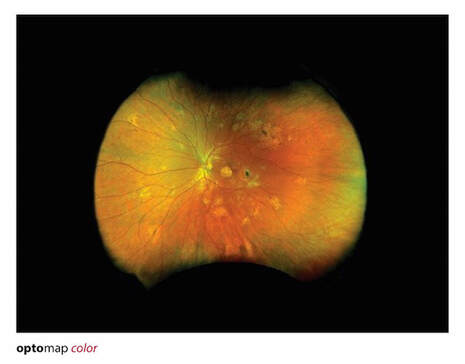

Retina Imaging/ Optos Monaco with OCT

Optomap retina imaging

OCT= Optical Coherence Tomography: uses light waves to take cross-section images of the retina, macula, optic nerve.

Optos Monaco combines optomap ultra-widefield technology with SD-OCT creating a fast, convenient, multi-modal imaging tool. Monaco can produce a 200°, single-capture retinal images of unrivaled clarity and can display a six-image overview including color, AF, and OCT of both eyes in as little as 90 seconds.